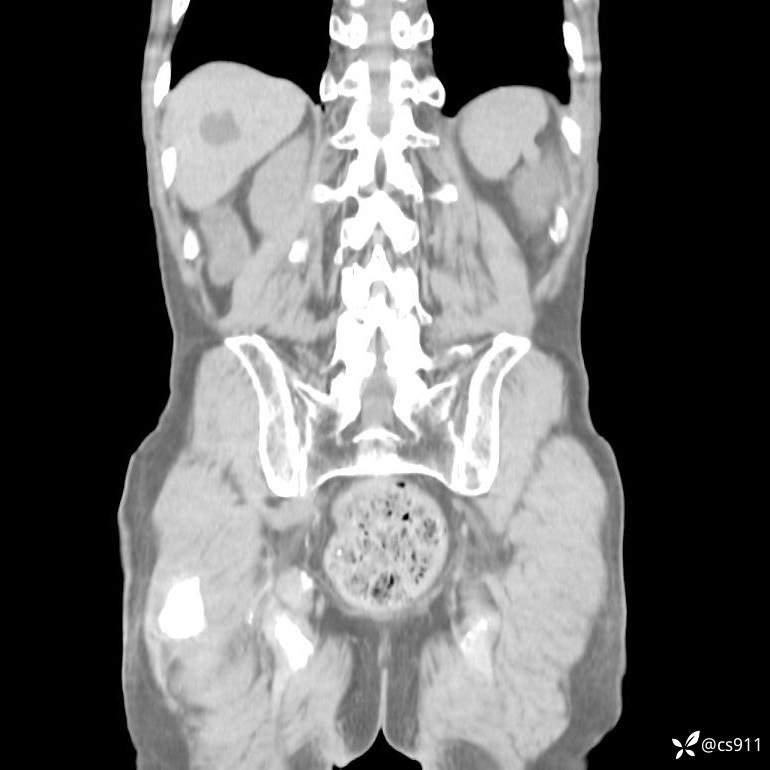

急腹症之急诊CT,原因?答案公布

男,77岁,腹痛、腹胀伴恶心呕吐1天。呕吐胃内容物,非喷射性呕吐,有咖啡色样胃内容物,诉有胃穿孔病史。查体:全腹平,下腹部压痛,全腹无反跳痛,叩诊呈浊音,移动性浊音阴性,肠鸣音减弱,1-2次/分。肛检:直肠未扪及明显肿物,可触及大量粪块。

T 36.6℃ P 80次/分 R 26次/分 BP 100/60mmHg

白细胞(WBC) H 14.55 10e9/L 4-10

红细胞(RBC) 4.58 10e12/L 4.3-5.8

中性粒细胞百分率(NEUT%) H 85.7 % 40-75

血淀粉酶(AMY) HH 1859 U/L 35-135

癌胚抗原(CEA) H 27.44 ng/ml 0-5

呕吐物 潜血试验 * 阳性 阴性

患者轮椅入室检查神志清楚, 能配合摆位和呼吸